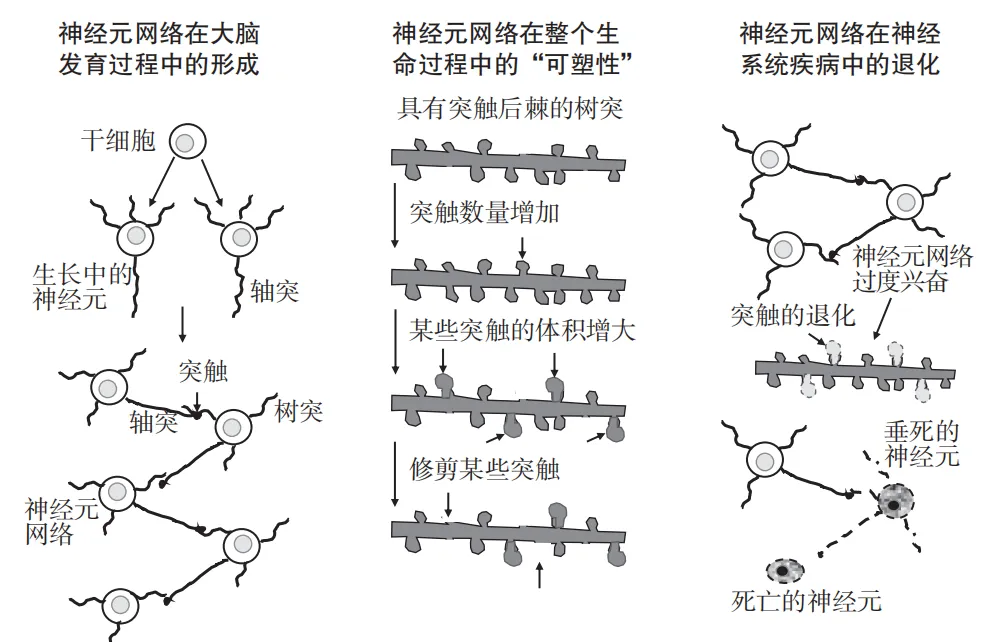

谷氨酸的作用远不止于此,在大脑发育的早期,甚至在神经元回路建立之前,谷氨酸就已经开始控制神经元的生长,并决定在哪里形成突触。

一旦神经元网络形成,谷氨酸就会开始调整神经元网络的结构,以便优化大脑的众多功能。

但也要小心,谷氨酸受体的过度激活会产生“兴奋性毒性”,这种毒性可以在癫痫发作、脑卒中和创伤性脑损伤时迅速发生,也可能在阿尔茨海默病、帕金森病等疾病中更隐蔽地发生。

此外,谷氨酸在许多神经系统疾病的发生中扮演了关键角色,包括阿尔茨海默病、帕金森病、肌萎缩侧索硬化(ALS)等。

阿尔茨海默病和帕金森病是两种常见的脑部神经退行性变性疾病,二者都涉及一种与谷氨酸受体过度激活有关的“慢性兴奋性毒性”,这是由患者大脑细胞能量代谢受损,同时伴有神经毒性蛋白的积累导致的。

还有另一种相对罕见但致命的疾病——肌萎缩侧索硬化(ALS)——也可能与谷氨酸能有关。

在病程早期,谷氨酸能上运动神经元的过度兴奋,可能导致下运动神经元的活动增加,因此患者通常会经历肌肉抽动和痉挛的症状。